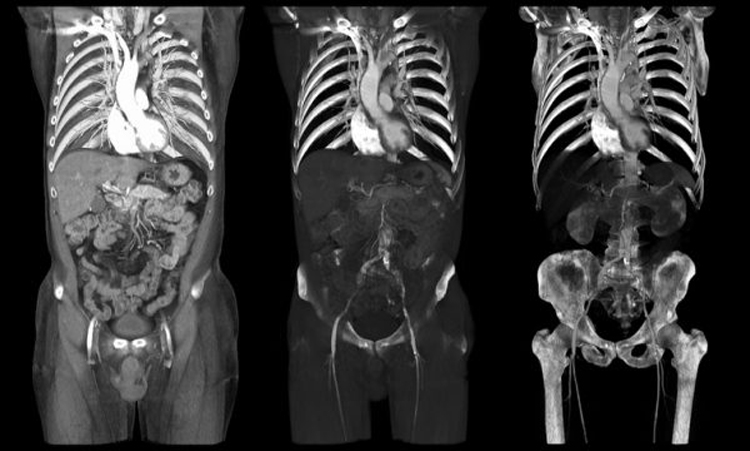

در مقایسه با روشهای سنتی که تنها تصاویری دو بعدی تولید میکنند، سی تی اسکن اسپیرال با چرخش تیوب اشعه ایکس به دور بیمار، امکان تولید تصاویری سهبعدی را فراهم میکند. این ویژگی به پزشکان این امکان را میدهد که ساختارهای داخلی بدن را به دقت بررسی کنند و در نتیجه تشخیصهای دقیقتری انجام دهند. این روش به ویژه در بررسی نواحی شکم و لگن که شامل اندامهای حساسی مانند روده، کبد و مثانه است، بسیار مؤثر است.

همچنین، سی تی اسکن اسپیرال میتواند با استفاده از مواد کنتراست، تصاویری با وضوح بالاتر تولید کند. این مواد معمولاً به صورت مایع یا گاز به بیمار تزریق یا بلعیده میشوند و به پزشکان کمک میکنند تا ساختارهای داخلی را بهتر مشاهده کنند. استفاده از این مواد کنتراست به ویژه در تشخیص بیماریهایی مانند تومورها، عفونتها و اختلالات عروقی اهمیت دارد و میتواند به بهبود دقت تشخیص کمک کند.

علاوه بر این، سی تی اسکن اسپیرال در تشخیص بیماریهای عروقی و قلبی نیز به کار میرود. با استفاده از این تکنیک، پزشکان میتوانند به بررسی عروق و شریانهای خونی پرداخته و مشکلاتی مانند انسداد یا نارسایی عروقی را شناسایی کنند. این اطلاعات به پزشکان در برنامهریزی برای درمانهای لازم و پیشگیری از عوارض جدی کمک میکند و به بهبود کیفیت زندگی بیماران منجر میشود.